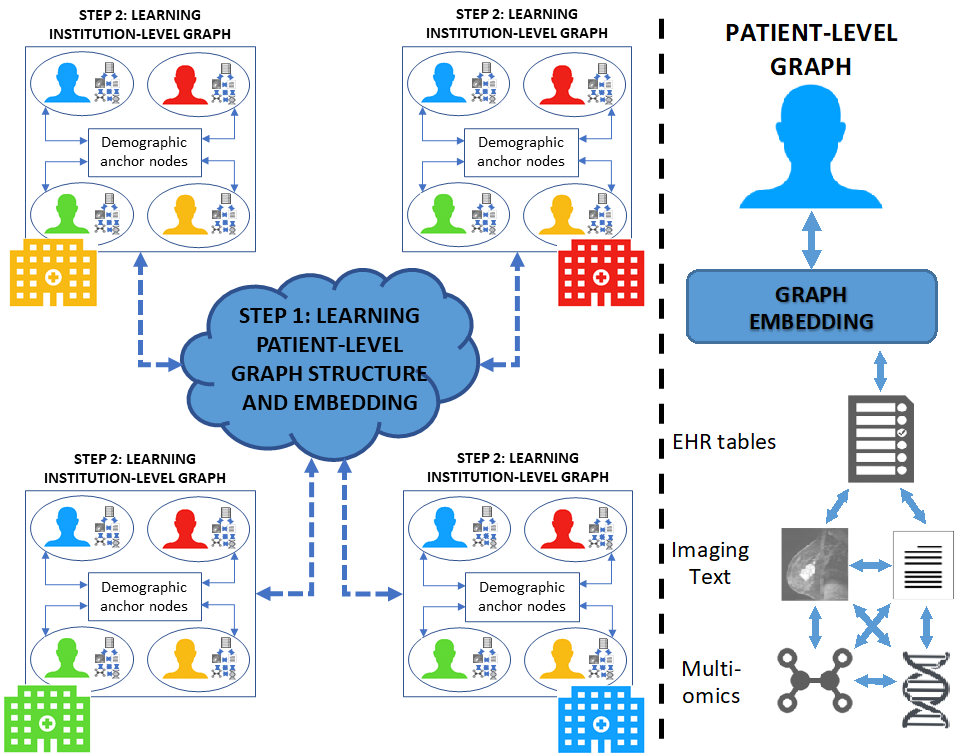

Therefore, for better precision medicine, physicians must now make increasingly complex therapeutic decisions with an unrealistic number of variables. Therefore, developments in artificial intelligence (AI) are envisioned to create a data science revolution in medicine. In particular, graphical neural networks (GNNs) have shown immense potential in learning meaningful and powerful data representations by combining the relational inference of graphical models with the power of deep learning. However, since the power of deep learning is strongly associated with data size and medical data cannot be easily shared among medical institutions due to patient privacy concerns, developing powerful GNN models for disease prediction in healthcare is a major challenge.

- (i) GNN models can be developed from the databases of multiple healthcare facilities, thereby increasing the size of the analyzed data; and

- (ii) data are always kept within the boundaries of each healthcare facility, thus avoiding data transfer.

The figures below provide an overview of the main research framework of the MEDomics UdeS lab.